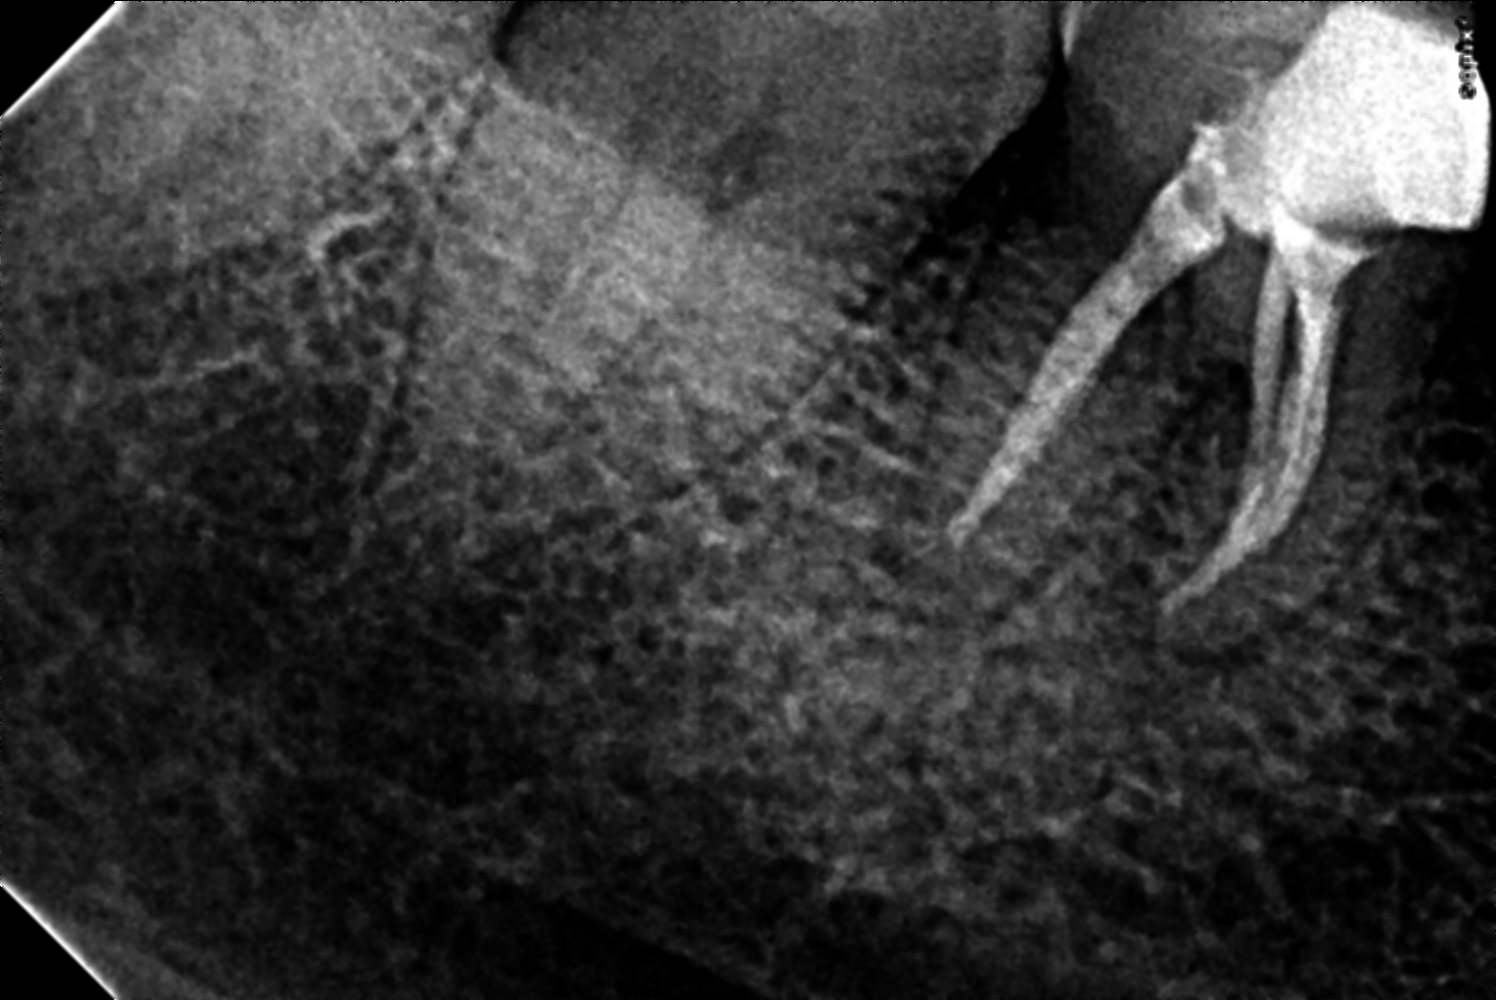

C/C & Rx plans46 acute pulpities

TreatmentsRCT 46 Done single visit

sealer adseal

distal ,mb,ml and mm

ml,and mm confluent